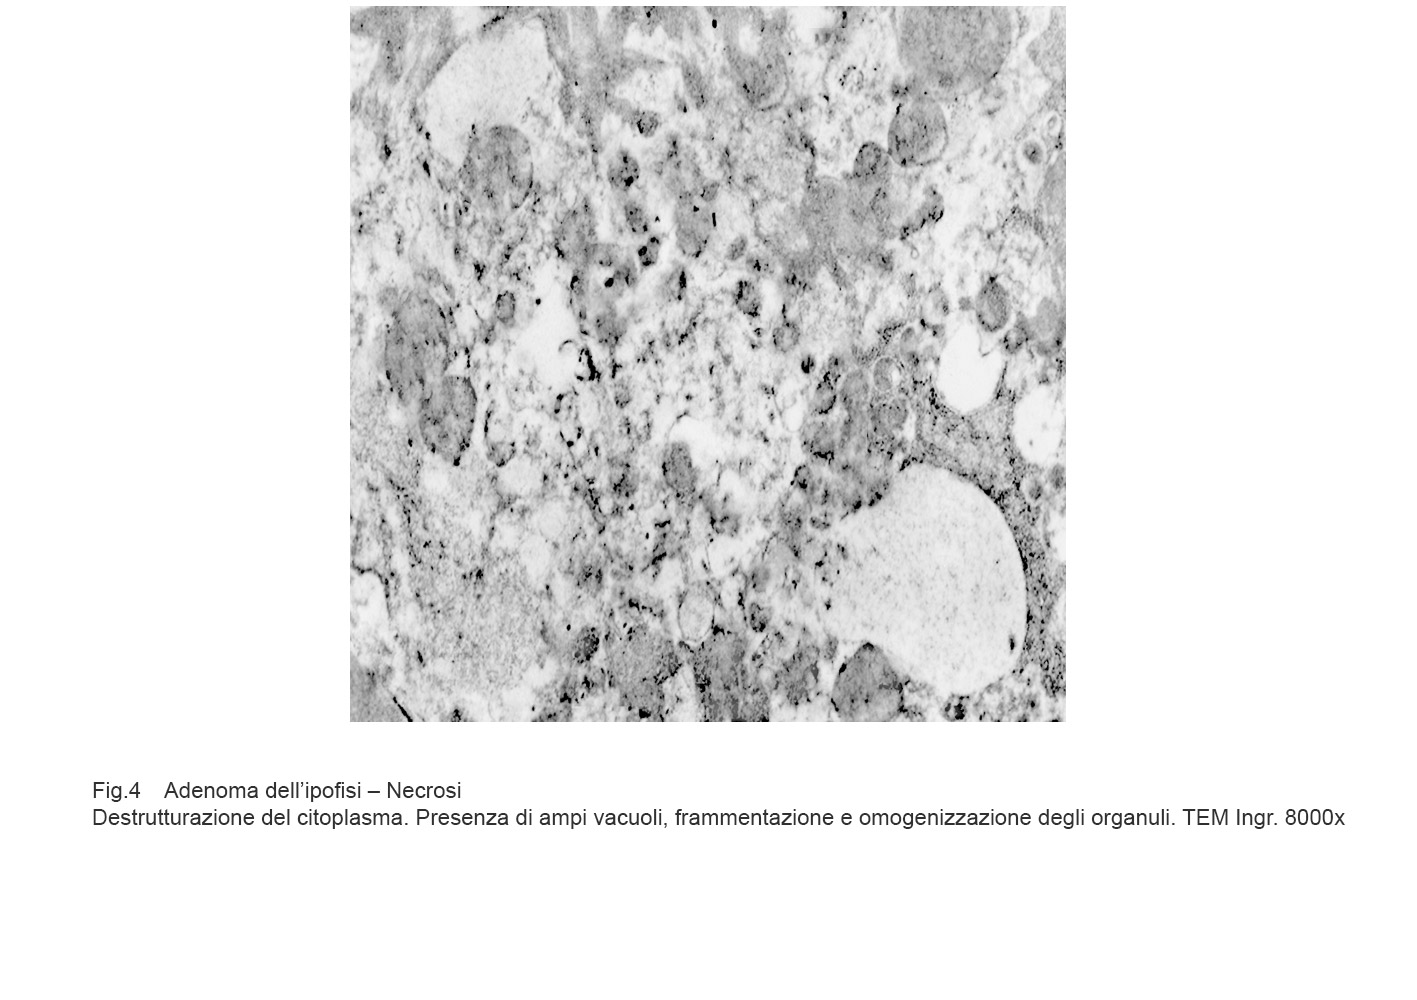

APPENDICE: NECROSI

La necrosi è un evento non programmato di morte cellulare; essa si manifesta attraverso fasi non controllabili di destrutturazione della cellula fino alla sua lisi.

Nel processo di necrosi, la cellula aumenta di volume, si rigonfia per il blocco delle pompe ioniche e conseguente penetrazione nel citosol di acqua e sodio.

Si ha il quadro di un processo vacuolare irreversibile pre-necrotico con disaggregazione dello assetto degli organuli intracitoplasmatici, grave rigonfiamento dei mitocondri, dilatazione abnorme delle cisterne del retico endoplasmatico, perdita dei ribosomi, disgregazione del nucleo per rottura della membrana nucleare.

Tali eventi sono progressivi, si condizionano reciprocamente e si concludono con la frammentazione delle substrutture, rotture della membrana plasmatica e sversamento del contenuto negli spazi intercellulari.

Fig.3  Fig.4

La presenza di enzimi lisosomiali in tale materiale in lisi provoca una risposta infiammatoria linfo-monocitaria con partecipazione di elementi macrofagici.